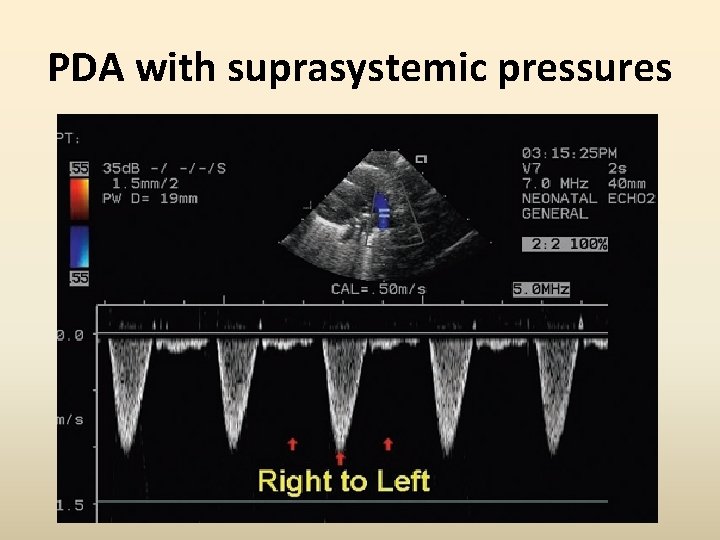

Increasing PA pressures Appearance of an early systolic R to L shunt with increasing PA pressures Widening and deepening of early systolic R to L shunt in parallel with a lesser L to R gradient.

PDA-Eisenmenger • Very difficult to demonstrate the Doppler flow • Corroborative evidence and clinical picture should guide suspicion : Septal flattening, RVH, dilated PA, high velocity PR etc • Contrast Echo : reveal bubbles in the descending aorta and not in the ascending aorta

PDA with suprasystemic pressures